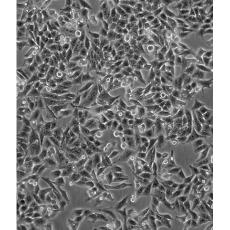

Hep-2 [Hep2]

中文名稱 人喉表皮樣癌細胞

組織來源 喉癌;女性

生長特性 adherent

形態特征 epithelial

細胞描述 最初認為這個細胞源自喉上皮癌,但隨后通過同功酶分析、HeLa標記染色體和DNA指紋分析發現,起源細胞已被HeLa污染。 角蛋白免疫過氧化物酶染色陽性。